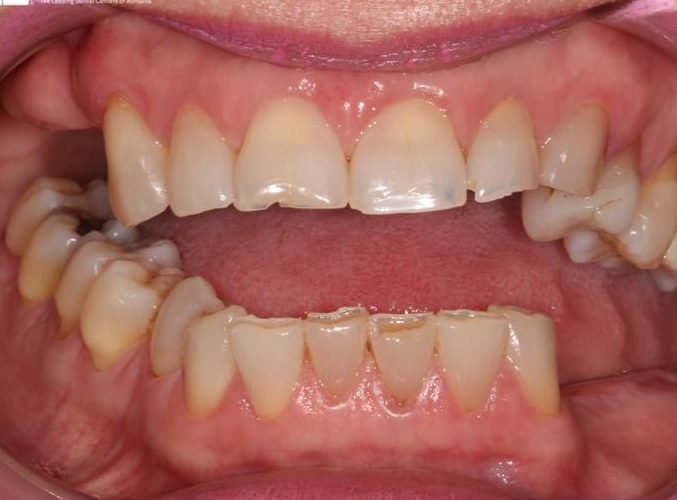

Pacienta in varsta de 52 de ani s-a prezentat in clinica noastra aflandu-se in cursul unui tratament implanto-protetic inceput in alta clinica. Pentru realizarea unor lucrari echilibrate ocluzal i s-a propus si realizat temporizare prin lucrari de PMMA (foto 3 si 4). Dupa 6 luni  s-au  realizat lucrari definitive din ceramica pe zirconiu (foto 5-10).